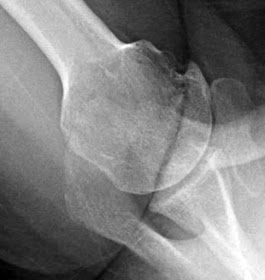

Degenerative joint disease is also known as osteoarthritis, osteoarthrosis or wear and tear arthritis. The pathogenesis of this condition results from the age-related loss of the ability of articular cartilage to sustain itself against seemingly minor mechanical imbalances and years of use. Degenerative joint disease typically affects healthy and active individuals. In our practice, most patients with degenerative glenohumeral degenerative joint disease are of Northern European ancestry in contrast to those of Asian, Southern European, Hispanic and African ancestry. In degenerative joint disease the glenoid cartilage and subchondral bone are progressively lost - either concentrically medially (more characteristic of female shoulders and those with inflammatory arthritis) or eccentrically posteriorly, with the articular cartilage often left intact anteriorly (more characteristic of male shoulders and those with degenerative joint disease or capsulorrhaphy arthropathy). The concern with the eccentric wear pattern is that the diminished articular contact area results in increased force/unit area leading to increased posterior wear which in turn leads to even less contact area. The cartilage of the humeral head is eroded in a Friar Tuck pattern of central baldness, often surrounded by a rim of remaining cartilage and osteophytes

The bone underlying the joint surfaces is usually sclerotic, but degenerative cysts can occur in the humeral head or glenoid; when severe, glenoid cysts may jeopardize the fixation of prosthetic glenoid components

Later on, osteophytes typically surround the anterior, inferior, and posterior aspects of the humeral head and the inferior and posterior glenoid. As a result, the humeral and glenoid articular surfaces may take on a flattened configuration that blocks rotation

We have named the commonly seen inferior humeral osteophyte the ‘goat’s beard’

Loose bodies are often found in the axillary or subscapularis recesses. The pathoanatomy of the arthritic glenoid may include medial erosion, posterior erosion, and retroversion along with varying degrees of posterior humeral subluxation. The triad of glenoid biconcavity, glenoid retroversion, and posterior humeral subluxation – the ‘bad arthritic triad’ - is commonly found in primary degenerative joint disease. Progressive contracture of the anterior capsule limits external rotation and compounds the tendency of the humeral head to translate posteriorly. Major biceps pathology and substantial rotator cuff defects are uncommon in patients with primary degenerative joint disease. The common clinical course is one of slowly progressive loss of the ability to sleep and to use the shoulder for work and recreation because of shoulder pain and stiffness.